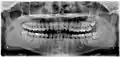

Зубы мудрости выделены зелёным цветом